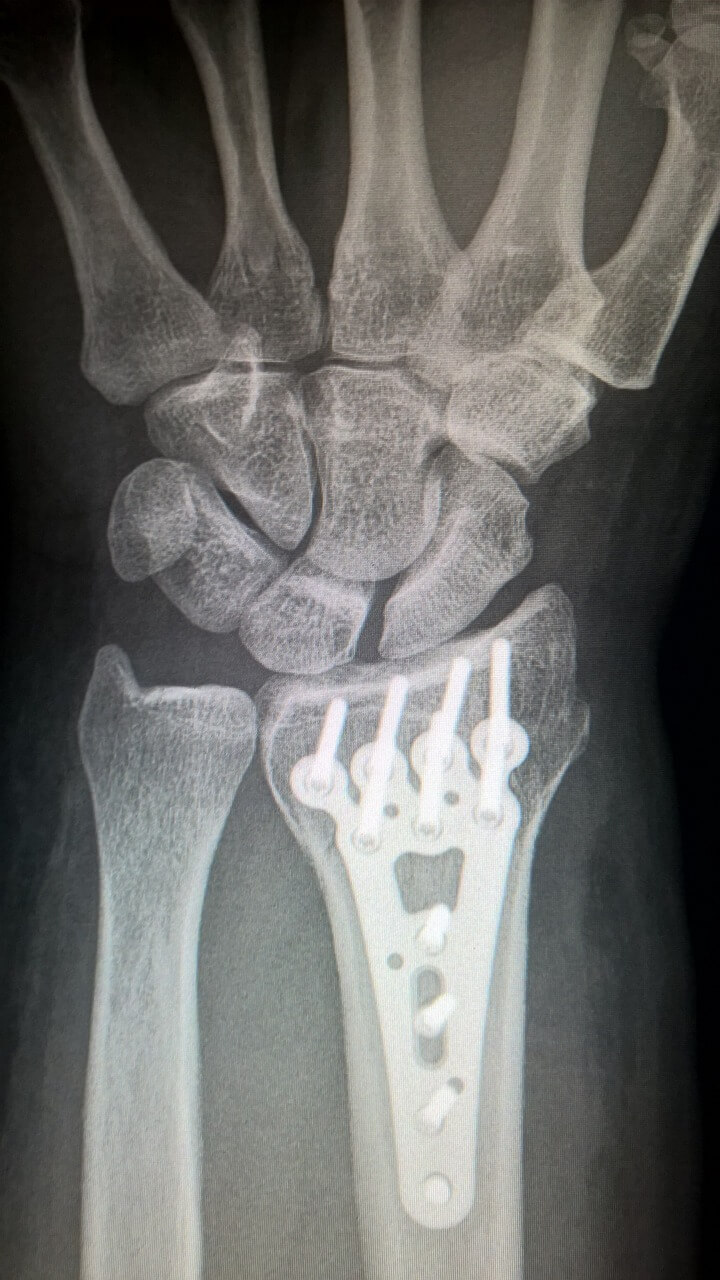

관절 영양제 추천 30대가 넘는 성인이거나 60대가 넘으셨다면 관절 영양제 복용을 통해 얼마든지 건강한 관절을 유지하며 삶을 즐기실 수 있습니다. 더불어 올바른 식습관과 꾸준한 운동, 적절한 관절 영양제 복용은 풍요로운 노후를 위한 중요한 요소입니다. 지금 관절 상태를 점검해보시고, 관절 가동성 또는 통증 등 문제가 있다면 지체없이 가까운 병원을 내방하셔서 상담받아보시기 바랍니다.